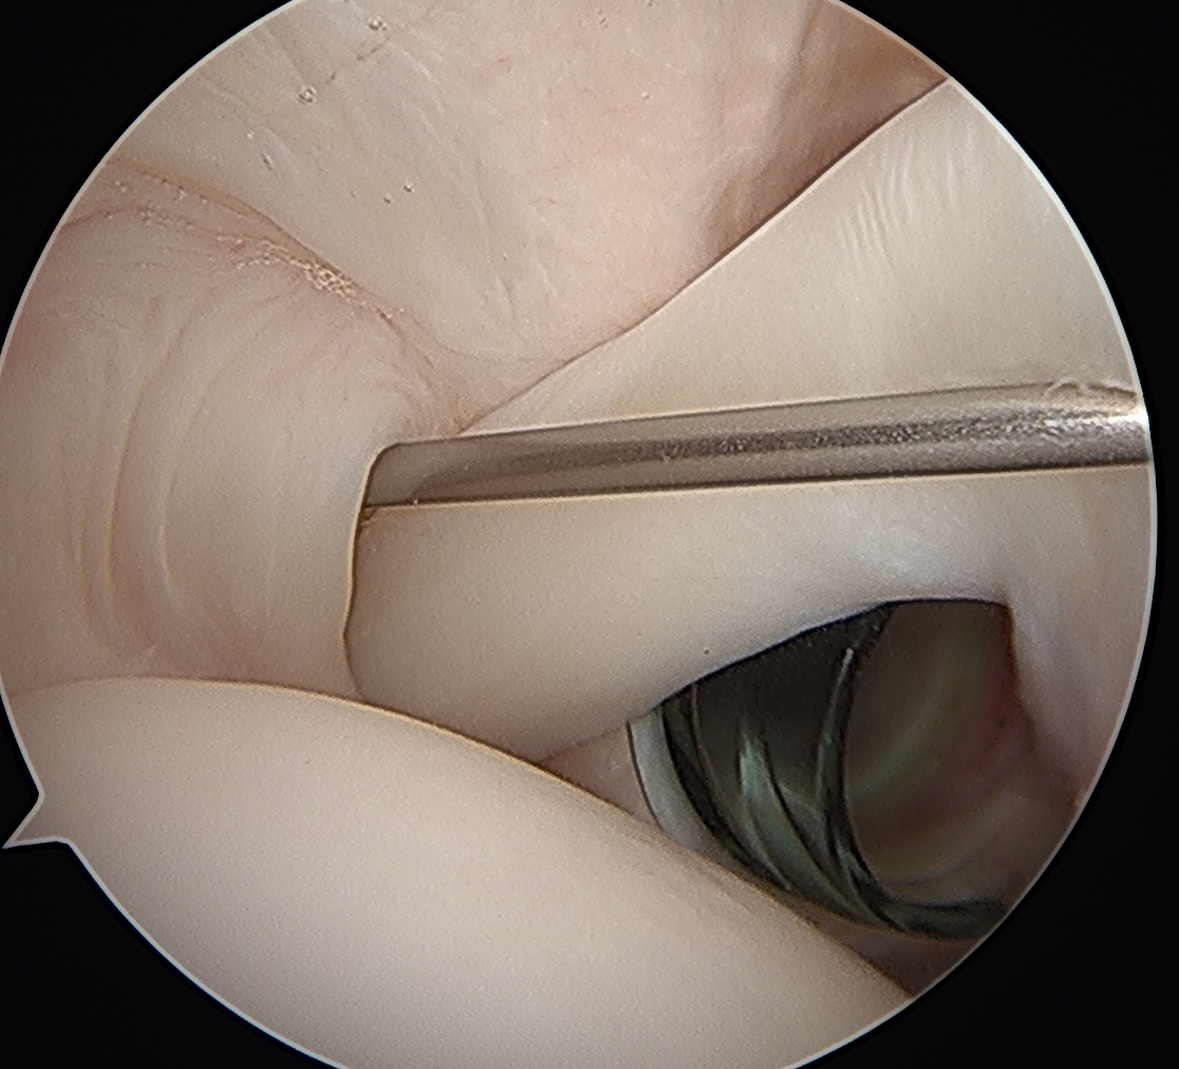

Arthroscopy

Tendonopathy

Medial subluxation of LHB